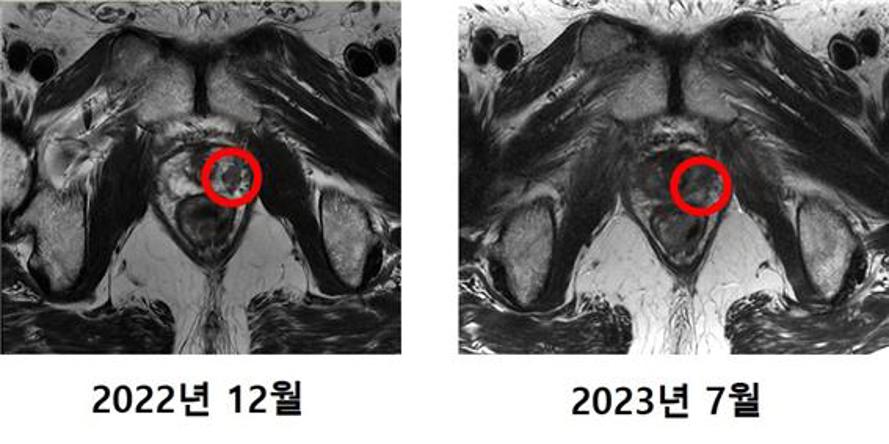

첫 중입자치료 환자 MRI 비교 사진. 사진=연세의료원

4월 말 치료를 시작한 최씨는 한 주에 3~4회씩 총 12번의 치료를 거쳐 5월 중순 모든 치료를 마쳤다. 치료 후 최씨의 PSA 수치는 0.01ng/mL 미만으로 떨어졌고, MRI 촬영 결과 암 조직은 발견되지 않았다.